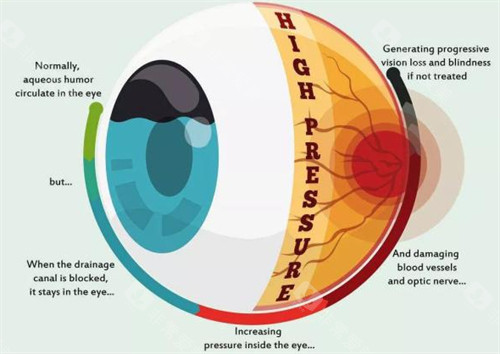

北京青光眼手术优选指南:朝聚眼科、民众眼科、普祥眼科、希玛林顺潮眼科、茗视光眼科五家机构凭借技术优势与口碑积累,成为青光眼患者关注的焦点。

北京青光眼手术领域正经历“比较准化、小创口化、个性化”的技术升级。

朝聚眼科的小创口技术、民众眼科的全术式覆盖、普祥眼科的疑难病例攻坚、希玛林顺潮眼科的国内外术式本土化、茗视光眼科的比较准检查体系,共同构建起多层次诊疗网络。

患者可根据自身病情重度程度、手术耐受性、术后改善需求等因素,选择比较适合的医疗机构。

随着3D打印、人工智能等技术的融入,青光眼手术的比较准度与可靠性将持续提升,为患者带来更多光明希望。